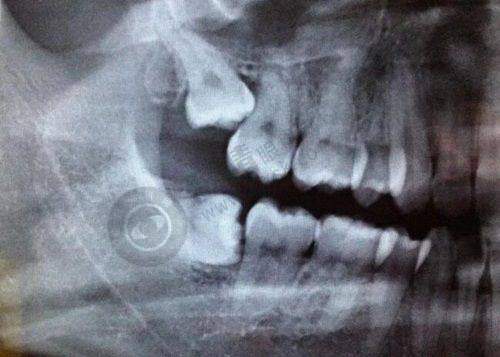

在擅长项目方面,正畸和种植牙都特别受欢迎,像金属隐形牙齿矫正、全口半口种植牙等都是其特色项目。

其技术优势明显,数字化种植技术十分出色。它利用计算机辅助让患者在种植前就能感受种植后的变化,检测数据更精细,方便医生设计合理的诊疗方案。在牙齿矫正方面,会按患者口腔情况进行定制化治疗,对龅牙、地包天等牙齿畸形问题改善成效好,矫正后牙齿功能性加强,牙套适配度高。

在技术设备上,引进了国内外精良牙齿矫正技术和设备,如CBCT、iTero扫描仪、隐形矫正等,可精细诊断口腔问题,制定个性化矫正方案。

专精团队拥有多年牙齿矫正经验,采用国内外精良矫治技术,提供金属托槽矫正、自锁托槽矫正、隐形矫正等多种选择。

技术设备上,引进了德国精良的数字化矫治系统,矫正精细效率高。